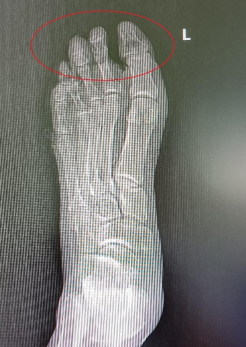

近大半年,陈大叔病情加重,左脚出现反复红肿和伤口渗液,疼痛难忍。他在当地医院治疗后伤口一直不能愈合,逐渐出现大部分足趾坏死、足部溃烂发黑的情况,足部体温因缺血无法测出,甚至连骨头都清晰可见。

术前足部体温因缺血已无法测出

术前前足组织坏死,骨外露